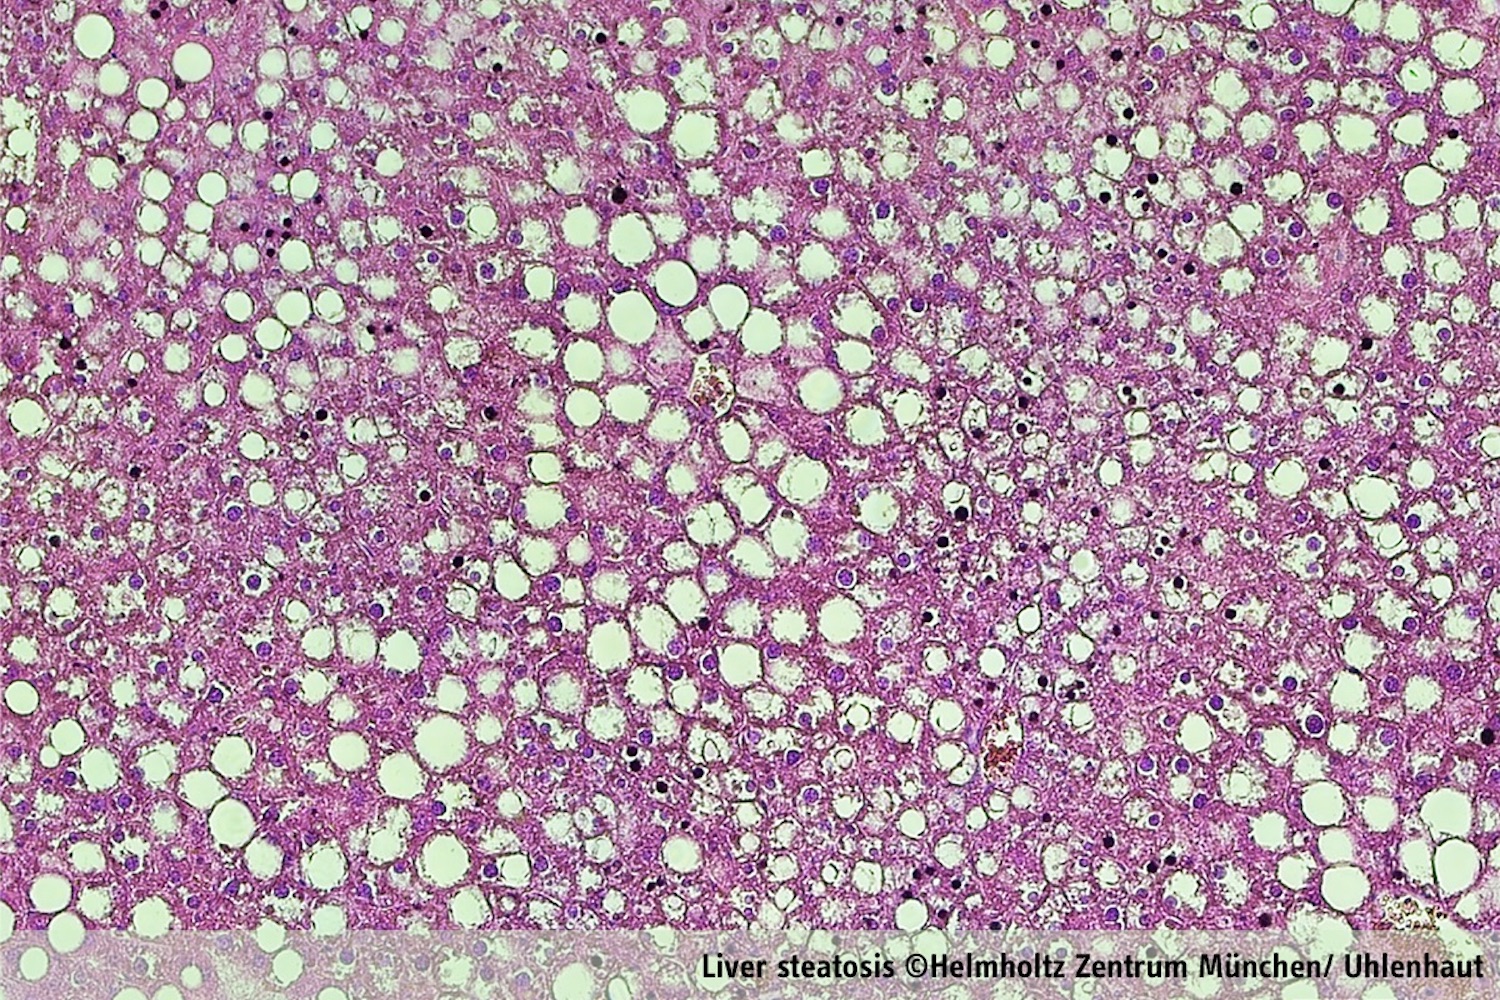

Jede Zelle im menschlichen Körper wird von einer inneren Uhr angetrieben, die dem zirkadianen Rhythmus von 24 Stunden folgt. Sie verläuft synchron zum natürlichen Zyklus von Tag und Nacht, hauptsächlich gesteuert durch Sonnenlicht, aber auch durch soziale Gewohnheiten. In einem gesunden System produziert die Nebenniere jeden Morgen Glukokortikoidstresshormone. Die Freisetzung von hohen Mengen an Glukokortikoid vor dem Aufwachen veranlasst den Körper, Fettsäuren und Zucker als Energiequellen zu nutzen. Dies ermöglicht es uns, in den Tag zu starten. Bei Störungen des zirkadianen Rhythmus (z.B. durch Schichtarbeit oder Jetlag) und/oder bei Veränderungen des Glukokortikoidspiegels (z.B. durch das Cushing-Syndrom oder langfristige klinische Behandlung) können schwerwiegende metabolische Dysregulationen wie Fettleibigkeit, Typ-2-Diabetes oder Fettlebererkrankungen auftreten. Ziel des Forschungsteams war es daher, die Bedeutung der täglichen Ausschüttung großer Mengen an Stresshormonen, den Einfluss dieser Hormone auf unsere innere Uhr und ihre Rolle für die täglichen Stoffwechselzyklen zu verstehen.

Um die metabolischen Funktionen der Glukokortikoide in der Leber zu untersuchen, charakterisierten die Forschenden die Aktivität ihres Rezeptors, des so genannten Glukokortikoidrezeptors, mit neuen Hochdurchsatz-Technologien. Alle vier Stunden, Tag und Nacht, analysierten sie die Leber von Mäusen. Die Mäuse wurden entweder mit normaler oder fettreicher Nahrung gefüttert. Mit Hilfe modernster Verfahren aus der Genomik, Proteomik und Bioinformatik konnte das Team sich dann ein Bild davon machen, wann und wo der Glukokortikoidrezeptor seine metabolische Wirkung entfaltet. Die Forschenden analysierten die Auswirkungen der täglichen Schwankungen der Glukokortikoidfreisetzung im 24-Stunden-Zyklus des Leberstoffwechsels. Sie konnten veranschaulichen, wie Glukokortikoide den Stoffwechsel beim Fasten (wenn die Mäuse schlafen) und bei der Nahrungsaufnahme (wenn sie aktiv sind) durch zeitabhängige Bindung an das Genom unterschiedlich regeln. Die Studie zeigt außerdem, wie die Mehrheit der rhythmischen Genaktivität durch diese Hormone gesteuert wird. Bei Verlust dieser Kontrolle (bei sogenannten Knockout-Mäusen) wirkt sich dies auf die Zucker- und Fettwerte im Blut aus. Dies erklärt, wie die Leber den Zucker- und Fettgehalt im Blut bei Tag und Nacht unterschiedlich steuert.

Glukokortikoide sind eine Gruppe von natürlichen und synthetischen Steroidhormonen wie Cortisol. Sie besitzen hochwirksame entzündungshemmende und immunsuppressive Eigenschaften, die die Aktivität des Immunsystems kontrollieren können. Daher werden sie in der Medizin weithin genutzt. Der größte Nachteil dabei ist, dass Glukokortikoide aufgrund ihrer Fähigkeit, den Zucker- und Fettstoffwechsel zu regulieren, auch schwere Nebenwirkungen verursachen können: Die Patienten können Fettleibigkeit, Hypertriglyceridämie, Fettleber, Bluthochdruck oder Typ-2-Diabetes entwickeln.